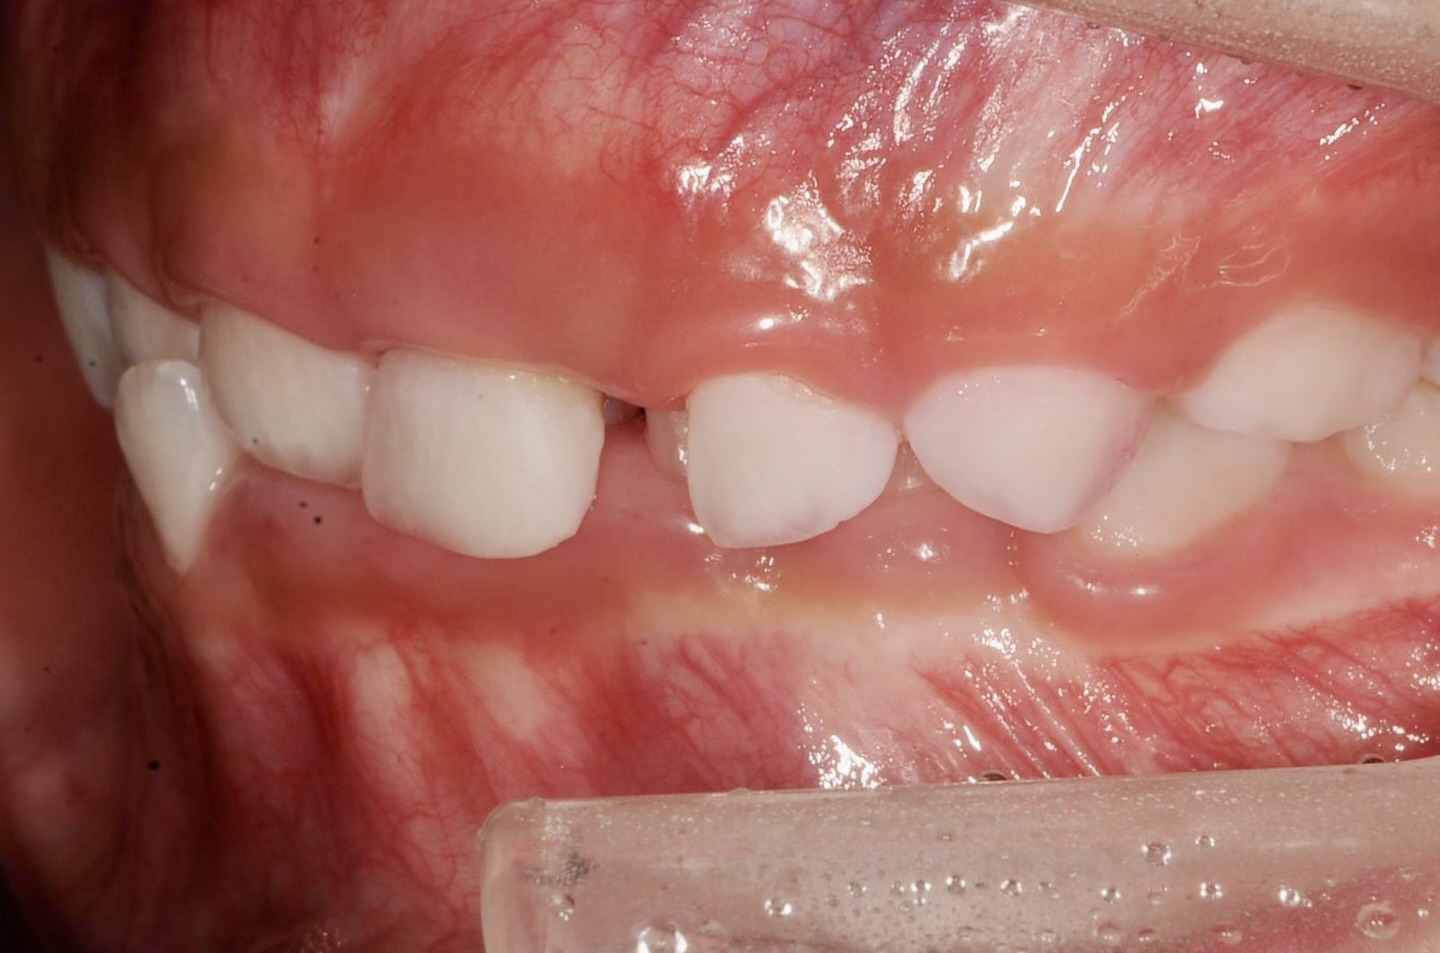

5歳 女児 小児矯正

歯並びの状態:

叢生(ガタガタ)

過蓋咬合(咬み合わせが深い)

BEFORE

AFTER

主訴

右下の歯が飛び出ているので治したい。

診断名・主な症状

過蓋咬合

治療内容

上下の歯並びの幅を拡げつつ、前歯の関係を改善しました。